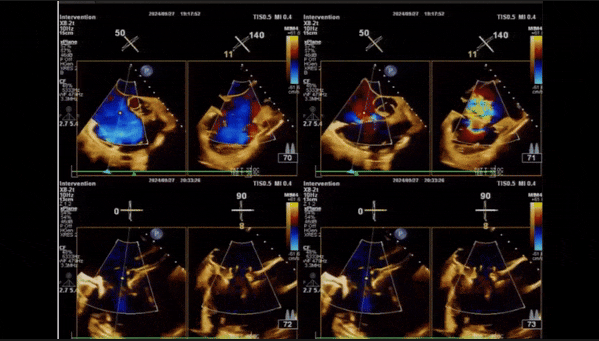

術后即刻返流

術后即刻返流三維

術中經食道超聲輔助下可見LuX-Valve Plus夾持件抓捕瓣葉狀態良好,夾持件在位,室間隔錨定位置良好,假體瓣膜整體錨定狀態穩固。

術前術后返流情況對比